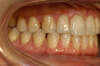

Cas d'orthodontie linguale, dents écartées

Vues avant le traitement